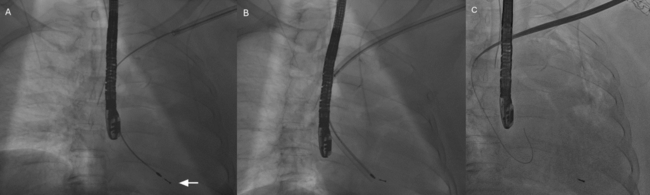

A 70-year-old woman with dementia, history of sick sinus syndrome, and permanent atrial fibrillation previously underwent dual-chamber transvenous pacemaker implantation. Over time, she developed Twiddler’s syndrome with repeated generator manipulation, resulting in diaphragmatic capture and recurrent pocket complications. The pacemaker system on the left side was extracted (Figure A-C). Intraoperative transesophageal echocardiogram was used to monitor potential lead extraction complications.